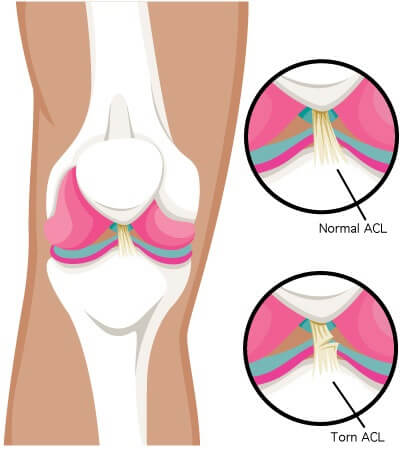

O LCA é composto por duas bandas de tecidos resistentes que ligam o fêmur (osso da coxa) à tíbia (osso da perna).

Ele passa pelo interior da articulação do joelho e cruza com outro ligamento importante — o Ligamento Cruzado Posterior (LCP) — formando um “X” no centro da articulação.

Essa disposição cruzada é o que dá origem ao nome “cruzado”.

A principal função do LCA é impedir que a tíbia deslize para frente em relação ao fêmur, mantendo a articulação estável e alinhada.

Além disso, ele atua como um estabilizador essencial durante movimentos rotacionais do joelho, evitando torções excessivas e protegendo as demais estruturas da articulação.

A lesão do Ligamento Cruzado Anterior (LCA) ocorre quando as fibras que compõem essa estrutura se rompem parcial ou totalmente.

A lesão do LCA ocorre quando o ligamento é esticado além do limite e se rompe parcial ou totalmente.